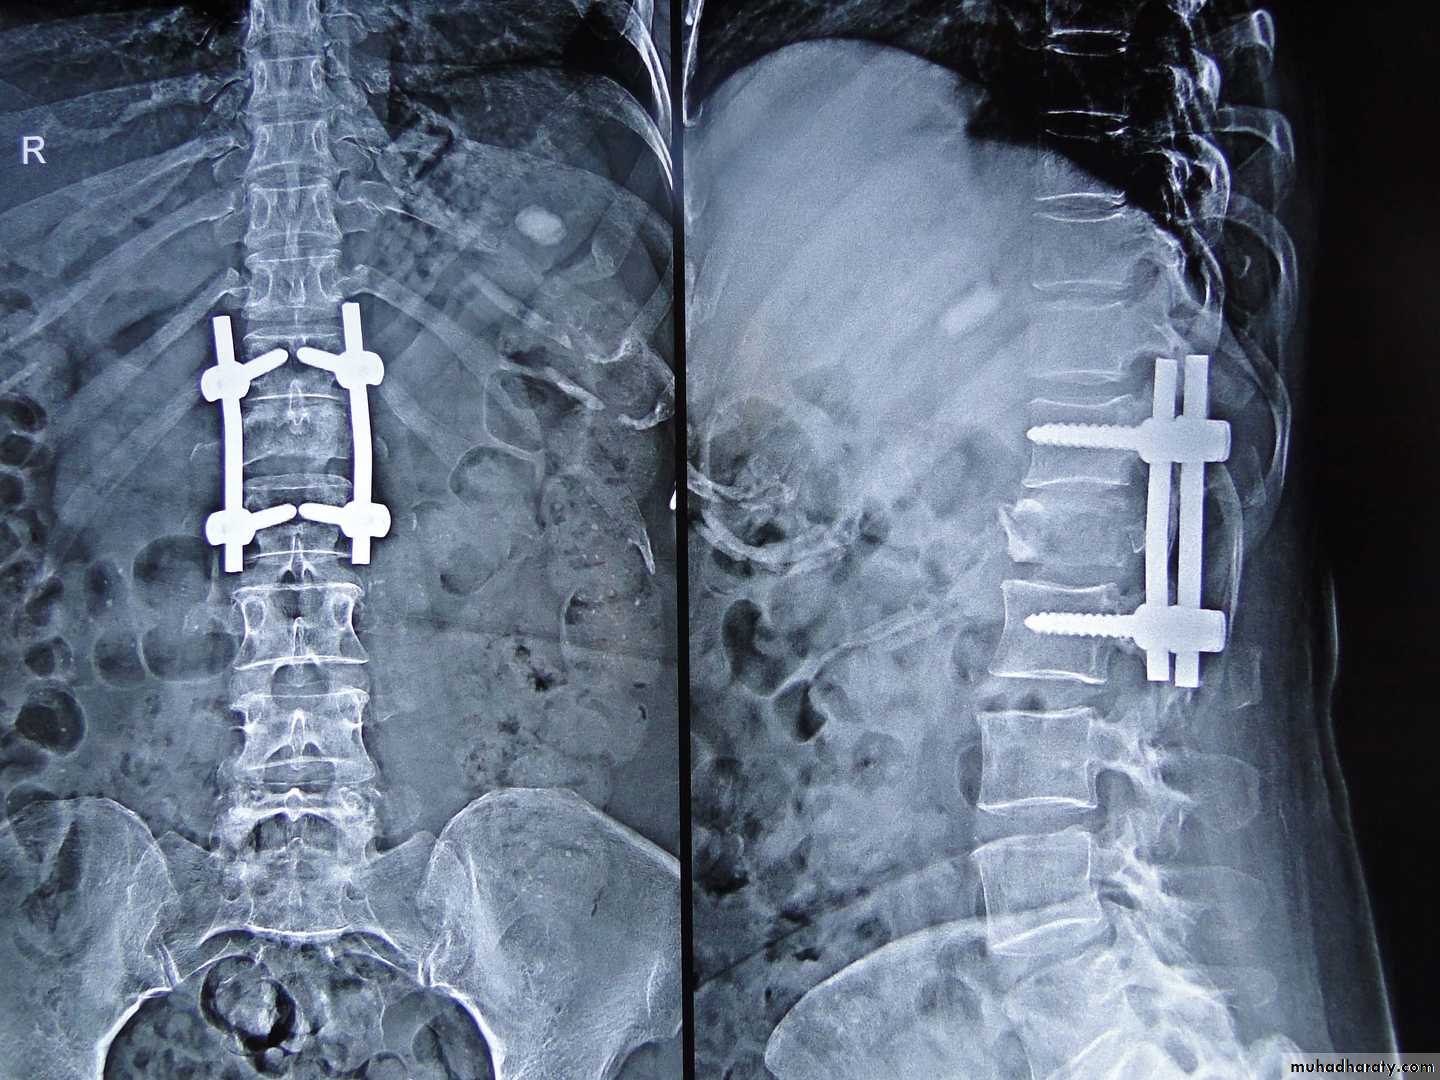

Operative treatment :

Ant. vertebral height loss > 50%.Canal compromise > 50%.

Kyphosis>20degrees.

Neural compression ( especially if progressive ).

Surgical options

Posterior FixationAnterior Fixation

Combination of both